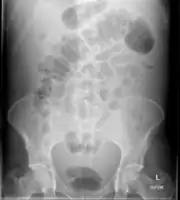

Diagnostic methodPhysical exam, ultrasound, CT scan[3]

In the developed world, the most common cause is liver cirrhosis.[4] Other causes include cancer, heart failure, tuberculosis, pancreatitis, and blockage of the hepatic vein.[4] In cirrhosis, the underlying mechanism involves high blood pressure in the portal system and dysfunction of blood vessels.[4] Diagnosis is typically based on an examination together with ultrasound or a CT scan.[3] Testing the fluid can help in determining the underlying cause.[3]

Diagnosis

Routine complete blood count (CBC), basic metabolic profile, liver enzymes, and coagulation should be performed. Most experts recommend a diagnostic paracentesis be performed if the ascites is new or if the person with ascites is being admitted to the hospital. The fluid is then reviewed for its gross appearance, protein level, albumin, and cell counts (red and white). Additional tests will be performed if indicated such as microbiological culture, Gram stain and cytopathology.[6]

Ultrasound investigation is often performed prior to attempts to remove fluid from the abdomen. This may reveal the size and shape of the abdominal organs, and Doppler studies may show the direction of flow in the portal vein, as well as detecting Budd-Chiari syndrome (thrombosis of the hepatic vein) and portal vein thrombosis. Additionally, the sonographer can make an estimation of the amount of ascitic fluid, and difficult-to-drain ascites may be drained under ultrasound guidance. An abdominal CT scan is a more accurate alternate to reveal abdominal organ structure and morphology.